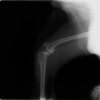

半年にわたる左後肢の跛行が認められるとのことで来院されました。触診にて左膝関節の疼痛、内側部の腫脹、膝蓋骨の内方脱臼を認めました。レントゲン検査にてfat pad signを伴う関節炎が認められたことから、前十字靭帯断裂と膝蓋骨内方脱臼( GradeⅢ)の併発と診断し、手術を行いました。術中の関節鏡検査にて前十字靭帯の完全断裂を確認、関節液検査にて感染を除外した後、TPLOと、滑車溝形成を始めとした膝蓋骨脱臼整復術を実施いたしました。

術前側面像

術前に25°であったTPAは、TPLO実施により7°に矯正されました。症例の歩行状態は良好です。